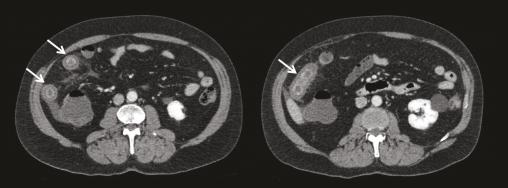

Iléite préterminale étendue se traduisant par un épaississement pariétal circonférentiel prenant le contraste (flèches). Extrait de : Vascularite à IgA de l’adulte